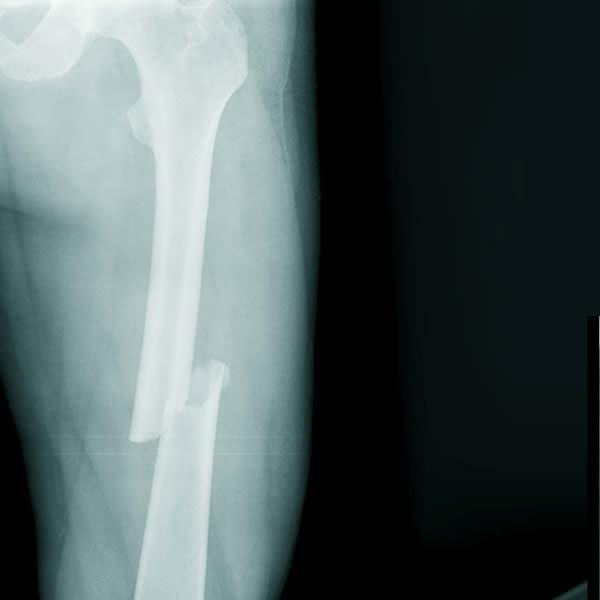

Gãy xương đùi

Xương đùi là xương dài và chắc, khỏe nhất trong cơ thể. Tuy nhiên, đoạn xương này vẫn có khả năng bị gãy nếu trực tiếp chịu tác động từ một lực lớn.

Tùy theo vị trí và mô hình gãy xương cũng như tình trạng thương tổn của các mô mềm (da, cơ, dây chằng…) xung quanh, gãy xương đùi được phân loại thành nhiều nhóm gồm:

• Gãy xương ngang (vết gãy xuyên qua trục xương đùi)

• Gãy xương xiên (vết gãy chạy dọc theo trục xương)

• Gãy xương xoắn ốc (đường đứt gãy bao quanh trục xương)

• Gãy xương nhiều mảnh (số lượng mảnh xương gãy được tìm thấy nhiều hơn ba)

• Gãy xương kín (da còn nguyên vẹn)

• Gãy xương hở (mảnh xương gãy chọc thủng qua da)

Tiếp theo, các chuyên gia sẽ tiến hành thăm khám lâm sàng để kiểm tra và đánh giá các dấu hiệu bất thường (đùi hoặc chân biến dạng, nứt da, các vết bầm tím hoặc mảnh xương xuyên thủng qua da…). Sau đó, người bệnh có thể làm thêm một số thủ thuật xét nghiệm hình ảnh như chụp CT hoặc chụp X-quang.

Dựa vào các kết quả thăm khám và xét nghiệm, bác sĩ sẽ đưa ra kết luận chẩn đoán cuối cùng cũng như hướng điều trị hiệu quả, phù hợp.